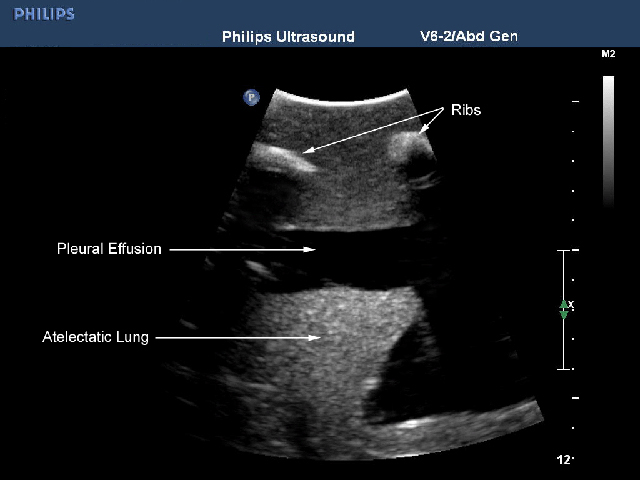

模型能够与任何超声影像检查设备连接使用,是练习提升经超声引导进行胸腔穿刺的理想模型。同时此模型还可用于练习非超声引导条件下胸腔穿刺,非超声引导胸廓造口术。